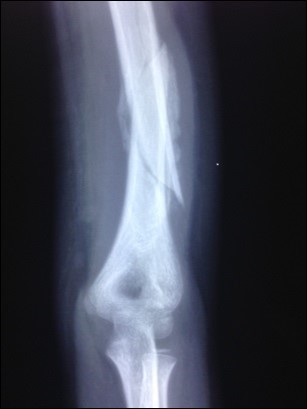

Figure 1.Partially united and angulated humerus shaft fracture prior to LLLT administration in one patient

Partially united and angulated humerus shaft fracture          prior to LLLT administration in one patient